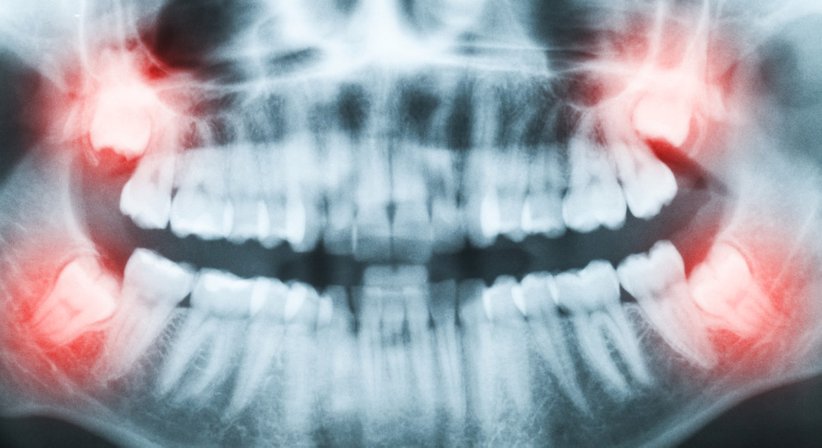

Wenn Weisheitszähne aufgrund von Platzmangel nicht durchbrechen, entzündet sind, oder verlagert (verdreht, gekippt) im Kiefer liegen, werden sie oftmals zu echten Problemfällen. So können retinierte oder verlagerte Weisheitszähne u.a. Zahnverschiebungen oder auch akute Infektionen mit Rötungen, Schwellungen und Schmerzen verursachen. Zudem können sich Zysten oder Abszesse bilden.

Treten solche oder ähnliche Beschwerden auf, sollte der Weisheitszahn umgehend entfernt werden.